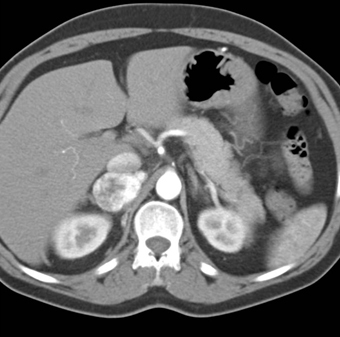

The best diagnosis in this case is?

adrenal lymphangioma

adrenal lymphoma

pheochromocytoma

adrenal carcinoma